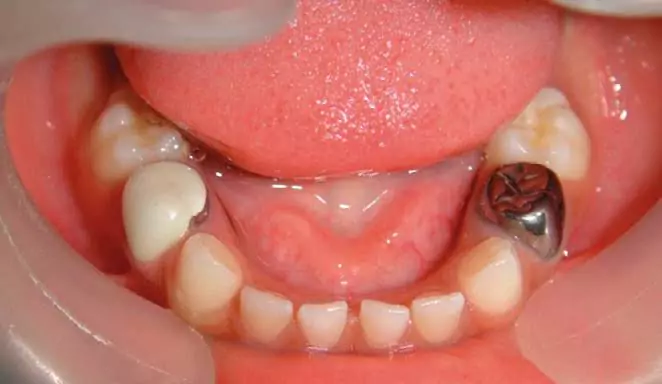

نمونه های درمانی ترمیم و روکش دندان شیری کودک با بیهوشی توسط دکتر نجمه اخلاقی